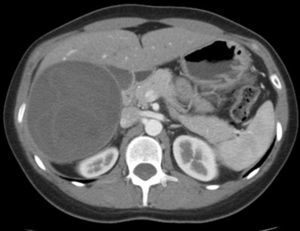

Todos los casos fueron diagnosticados en base a la historia clínica, examen físico, tomografía computada de abdomen (fig. 1) y test de ELISA. Para descartar hidatidosis pulmonar o un quiste en tránsito hepatotorácico se realizó una tomografía computada de tórax previo a la cirugía. Todos los pacientes fueron tratados con albendazol (10mg/kg/día) durante al menos 2 semanas previo a la cirugía y por 4 semanas en el postoperatorio.

Corte de tomografía computada que muestra a nivel hepático una gran lesión heterogénea de 10,5 por 9,3 cm de diámetro que comprometía los segmentos V y VI, con finas membranas internas compatible con un quiste hidatídico hepático. Dicho quiste estaba en íntimo contacto con la vena cava inferior.